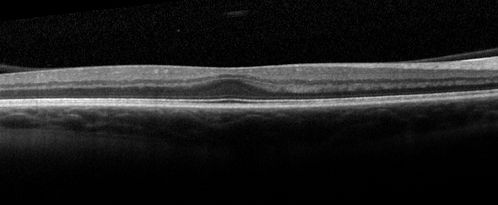

Foveal Hypoplasia in 23 year old patient with ROP

Foveal Hypoplasia - Retinopathy of Prematurity (ROP)